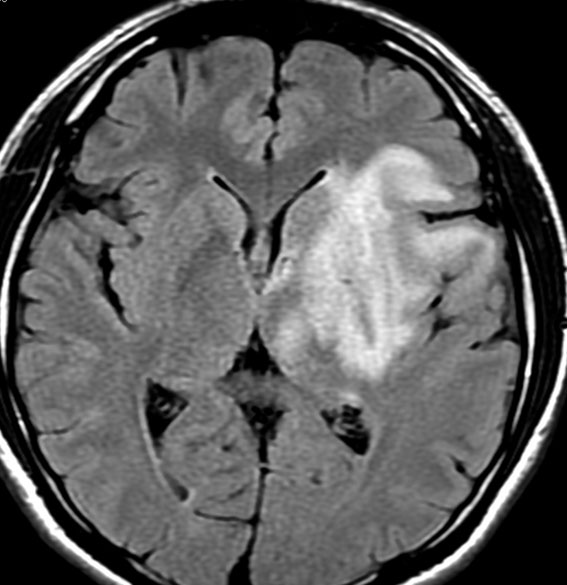

放射線治療後9週目

フレア画像です。たった2週間で脳浮腫が高度の脳浮腫となっています。失語症と右片麻痺と認知機能低下が生じました。ステロイド剤とグリセリンの点滴を行いました。